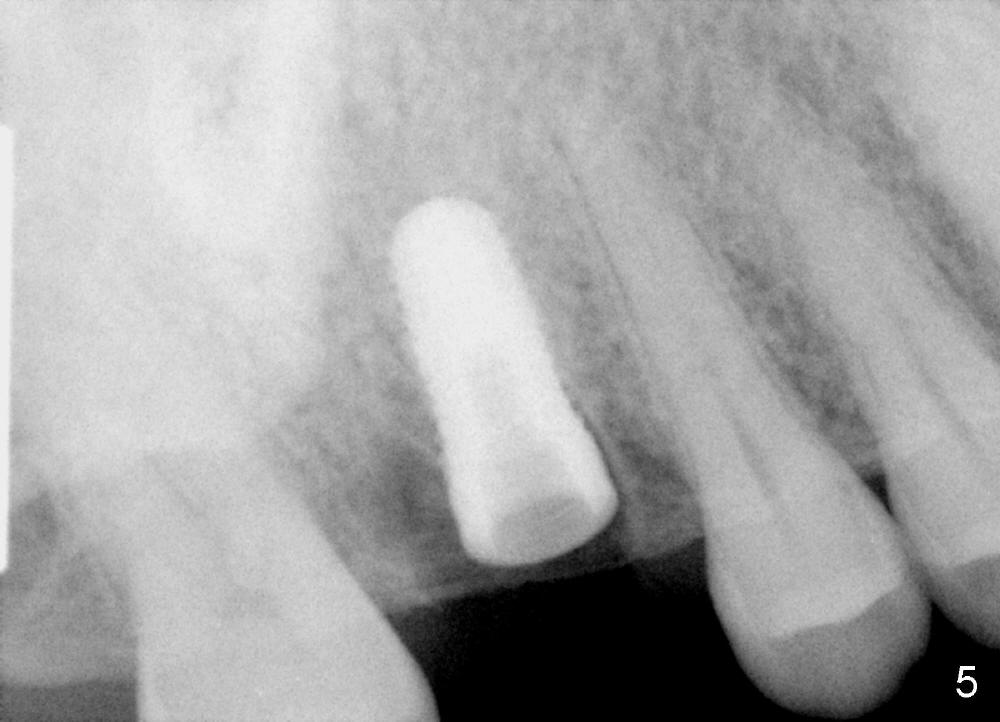

The tooth #3 has a crack line (Fig.1 ^). The septum (Fig.2 S) looks like an inverted pyramid (Fig.3), coronal part being pointed, whereas the apical broad. The shape of the septum is not so favorable to placement of tapered implant. Osteotomy starts with 1.5 mm pilot drill in the middle of the septum, followed by round tapered osteotomes 2 and 3 mm. The osteotomy begins to deviate into the mesiobuccal socket. The same osteotomes are used to re-direct the osteotomy palatally, followed by tapered drills, trying to move osteotomy palatally. A 4.5x17 mm tap is inserted with stability (Fig.4). Following using 5x17 mm tap at the depth of 12 mm, a 5.3x12 mm bone-level implant is placed ~ 1.5 mm below the crest, 1.5 mm above the septum (Fig.5). Demineralized cortical human allograft is placed in the remaining sockets and around the most coronal aspect of the implant (with a small piece of gauze placed in the implant well). After removal of the gauze, a piece of collagen membrane is pierced and carried by a 8.2x4/3 mm healing abutment and fixed in place (Fig.6 M). The periphery of the membrane is tucked underneath the gingiva. The wound is covered by perio dressing. The patient returns to clinic for follow up 8 days postop. There is no discomfort. In order to protect the collagen membrane (Fig.6), the perio dressing is intentionally not removed (Fig.7). Two weeks postop, the patient remains asymptomatic. After perio dressing removal, the membrane appears to have been resorbed (Fig.8 as compared to Fig.6). The bone graft (B), although exposed, remains in place and condensed, surrounded by healing healthy gingiva (*). The patient returns 2.5 months postop. The implant appears to osteointegrate (Fig.9, as compared to Fig.5). The buccal (Fig.10) and palatal (Fig.11) gingiva adapts to the healing abutment. When the healing abutment is removed for restoration 3 months postop, the gingiva looks healthy (Fig.12). A cemented abutment (5.8x4(2) mm) is placed; a crown is fabricated (Fig.13). The patient returns for recall 5 months post cementation. He reports food impaction distal to the crown. The gap mesial to the implant has closed (Fig.14).